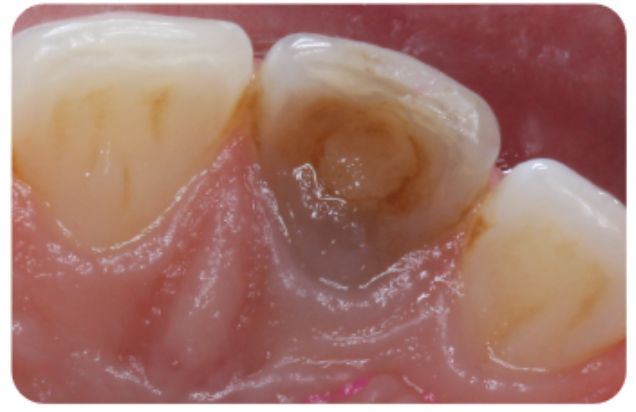

We can treat the yellow discolouration by external tooth whitening. But it may take longer to achieve a satisfactory result. A veneer might be necessary if a satisfactory result cannot be achieved with external whitening alone (Figure 1).

Figure 1: Pulp canal obliteration (PCO). The patient had trauma to UL1 15 years ago and developed a yellow discolouration over time. She was keen to improve the appearance of the tooth. The UL1 was asymptomatic and did not respond to sensibility testing.

Radiographically, UL1 had a normal PDL width and an intact lamina dura could be seen around the tooth. A diagnosis of pulp canal obliteration was reached for UL1. There was no endodontic infection and the patient was advised to have external tooth whitening; this will take longer and a veneer might be necessary if a satisfactory result can’t be achieved with external whitening alone. Figure 1a: Preoperative photograph. Figure 1b: Preoperative radiograph.